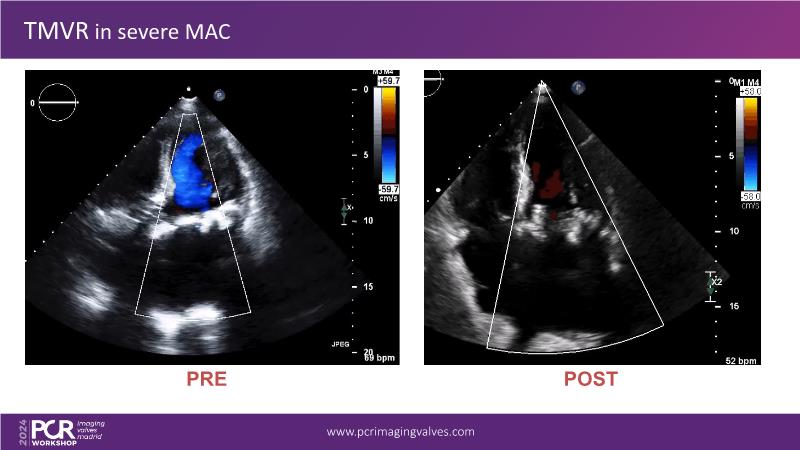

Explore cutting-edge transcatheter valve interventions for mitral and aortic valve disorders, including valve-in-valve procedures and management strategies for paravalvular leakages, and learn about diagnosing and treating mitral annular calcification and transcatheter options in infective endocarditis.